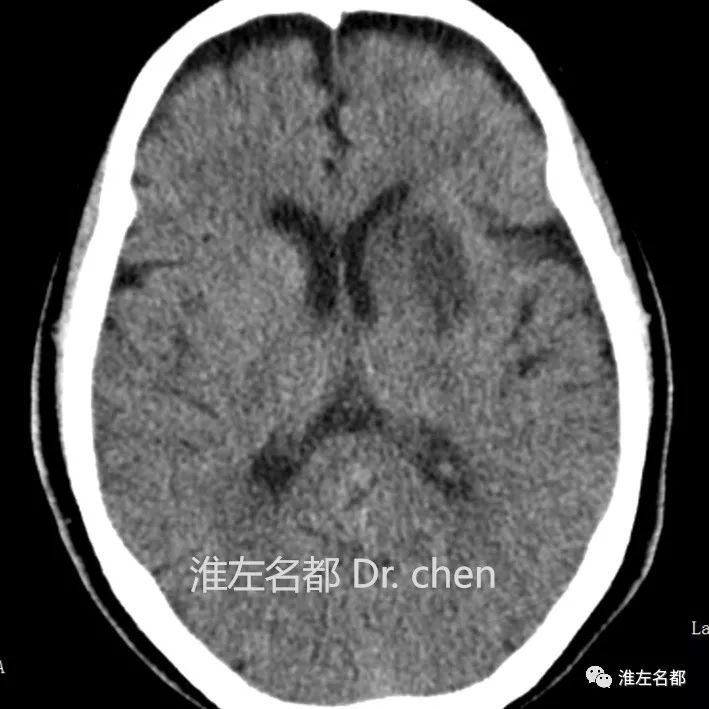

△CT平扫:左侧壳核前部和尾状核头部低密度梗死灶,

蛛网膜下腔出血高密度已转为等密度。